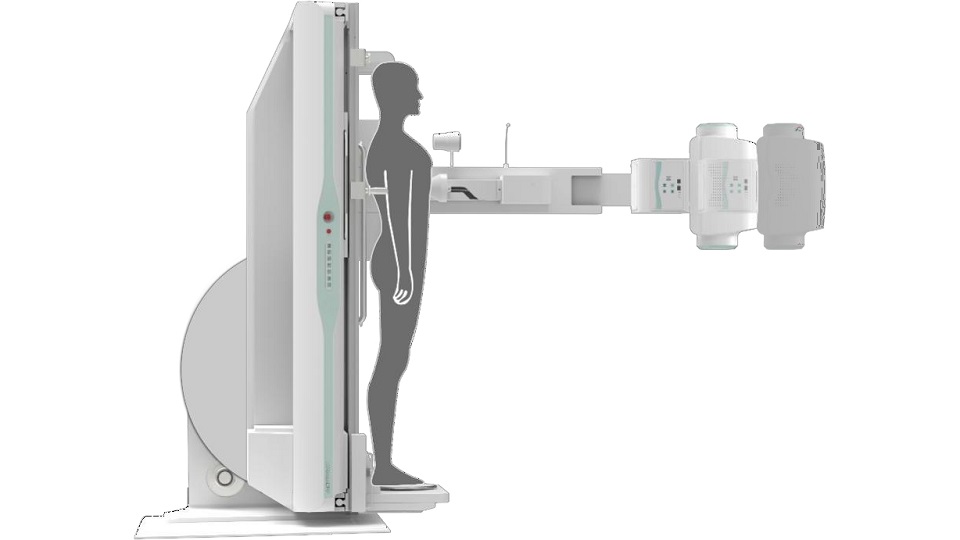

SID可自动拉伸至1.8 米,满足胸片、职业性尘肺病检查等摄影需求

点片装置可实现大范围纵向移动,高效完成各部位、全身拼接等检查需求

床体可实现-25°~0°~+90°的大范围旋转,满足不同体位检查需求